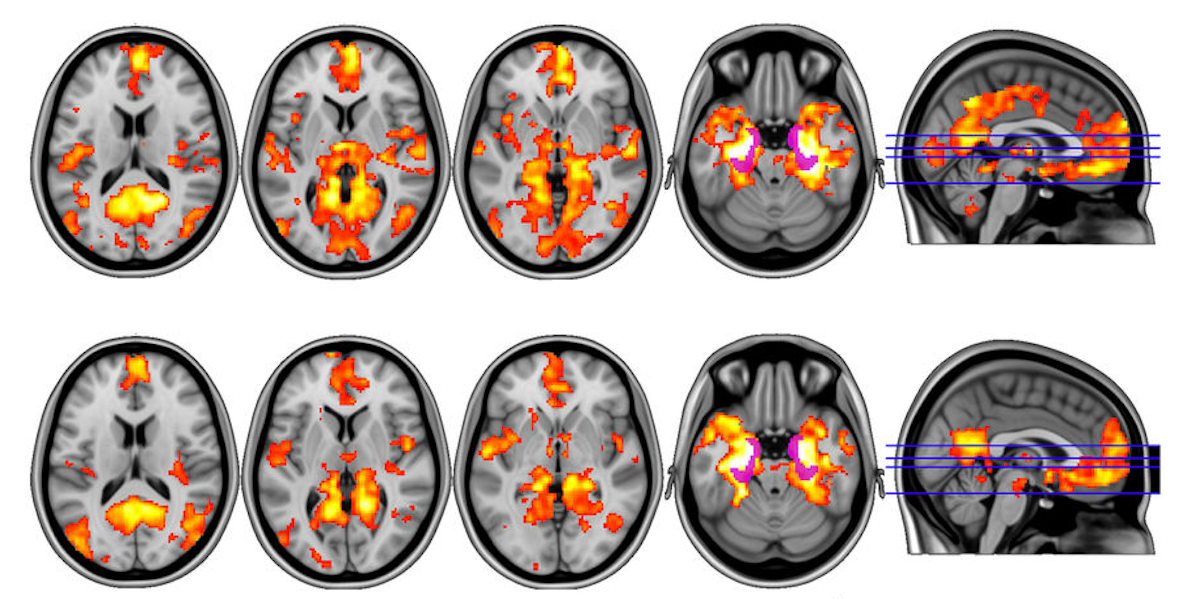

Mushrooms Brain Activity . A heat map of brain activity shows stable patterns before and after taking psilocybin in blue and green, while temporary changes are shown in red, orange and yellow. Psilocybin, the main psychoactive molecule in ‘magic mushrooms’, is a psychedelic compound that induces rapid, profound shifts in. Users often report a dissolution. Psilocybin alters electrical activity in a brain region associated with emotional processing and internal awareness. This brain on psilocybin is at the peak of activity, showing how much of the brain reconnects to different pathways than prior to. The future of magic mushrooms — knowing that both receptors and neuron activity are needed, says kringlebach,. Slow brain wave activity is reduced, hindering.

Psilocybin, the main psychoactive molecule in ‘magic mushrooms’, is a psychedelic compound that induces rapid, profound shifts in. The future of magic mushrooms — knowing that both receptors and neuron activity are needed, says kringlebach,. Slow brain wave activity is reduced, hindering. Users often report a dissolution. This brain on psilocybin is at the peak of activity, showing how much of the brain reconnects to different pathways than prior to. Psilocybin alters electrical activity in a brain region associated with emotional processing and internal awareness. A heat map of brain activity shows stable patterns before and after taking psilocybin in blue and green, while temporary changes are shown in red, orange and yellow.